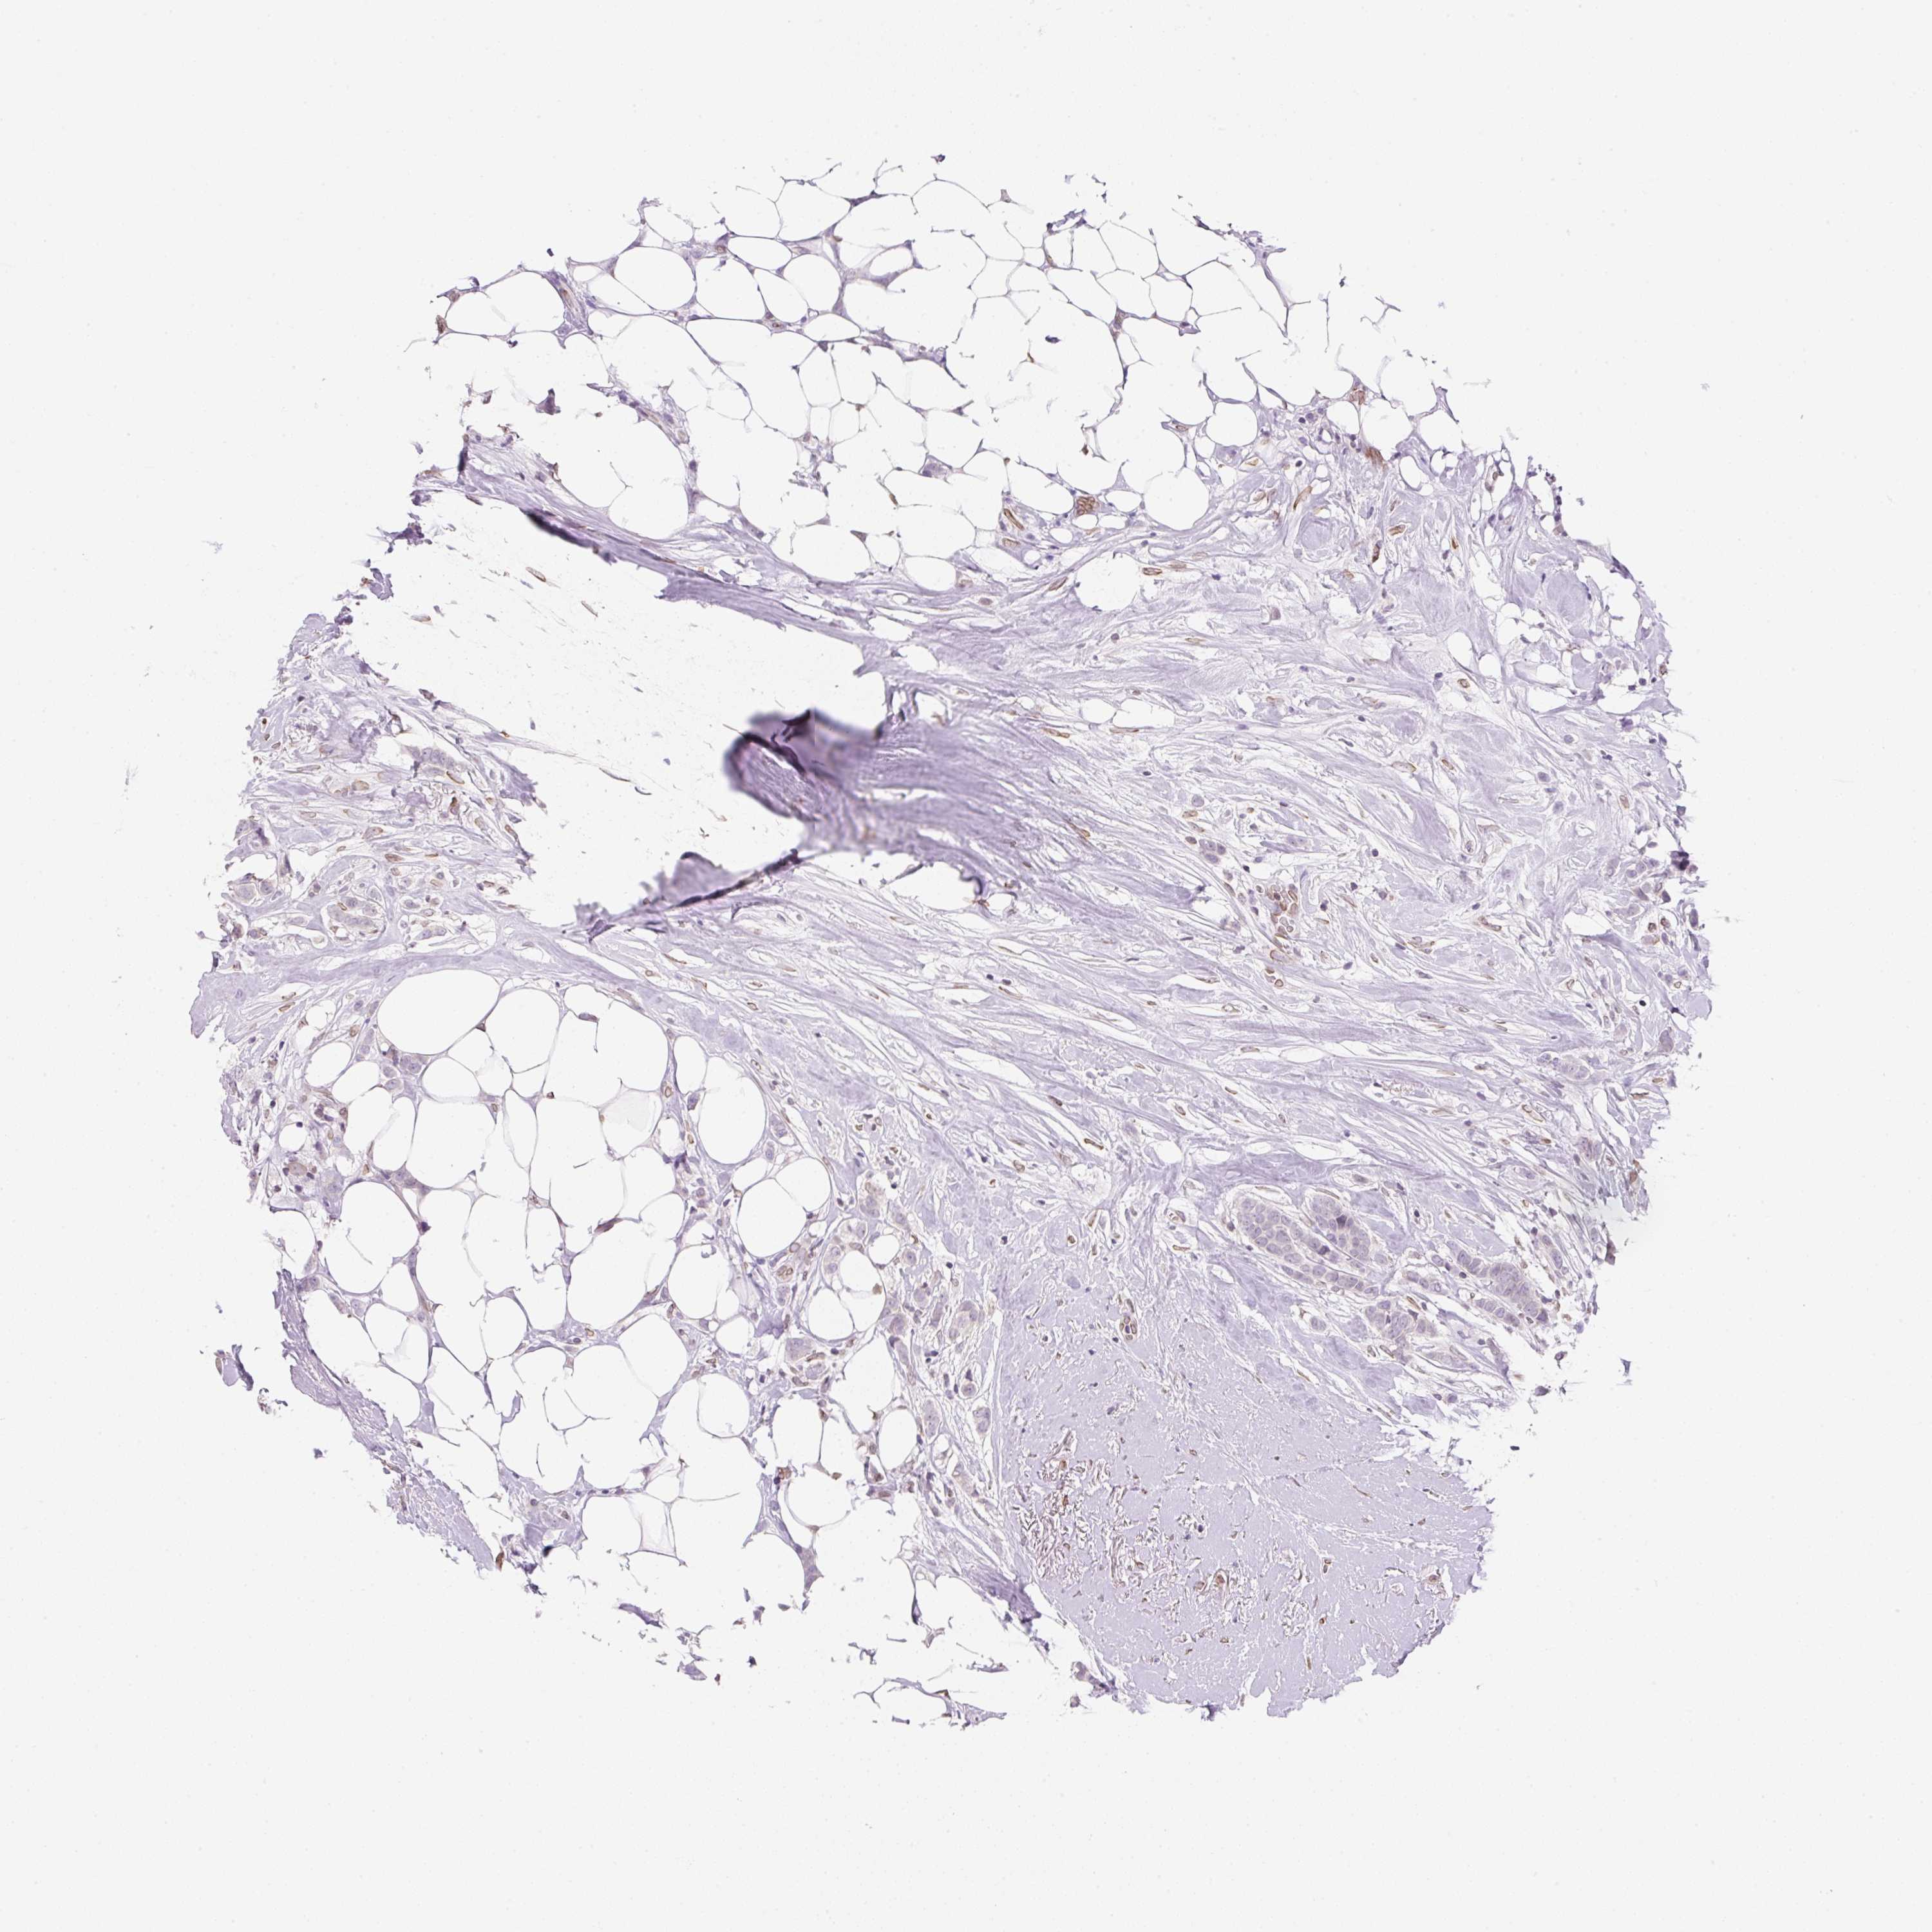

CANCER BREAST CANCER Show tissue menu

BRCA TCGA BRCA VALIDATION PROTEIN EXPRESSION